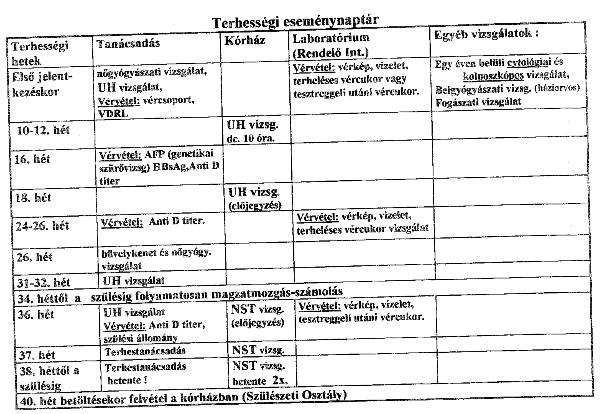

.Az embernek totál az agyára megy .D!.Citológia bizti jó,mert már szóltak volna!Nálatok is be kell jelentkezni a 18. heti UH-ra?Nálunk AFP szűrésnél már be kell jelentkezni...

Szt csináltasd meg a 12. heti UH-ot itthon,megmérik a tarkóredőt is,meg minden.Én legalább is megcsináltatnám.Tudod,nem akarok már semmit mondani az ottani vizsonyokra